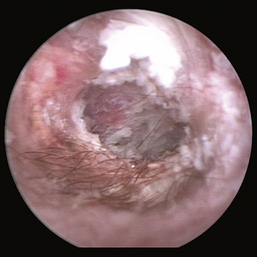

If the tympanic membrane is intact, then one must evaluate the tympanic membrane to determine whether it is abnormal or normal and couple that with the results from the radiographic imaging. A tympanic membrane, specifically the pars tensa, that is opaque, gray, peeling, bulging, or hemorrhagic would be considered abnormal. At times, it may be difficult to determine whether the “structure” that one is visualizing is indeed the tympanic membrane, exudate in front of the membrane, or, in the case of a ruptured tympanic membrane, middle ear structures. In those situations, I will pass an open-ended 3½F Tomcat catheter through the port on the otoendoscope and gently touch the structure in question.

image

Figure 20-11 Bulging pars tensa in a dog with otitis media.

(Courtesy of Dr. Lynette Cole, The Ohio State University, Columbus, Ohio.)

Figure 20-12 Scaly pars tensa in a dog with otitis media.